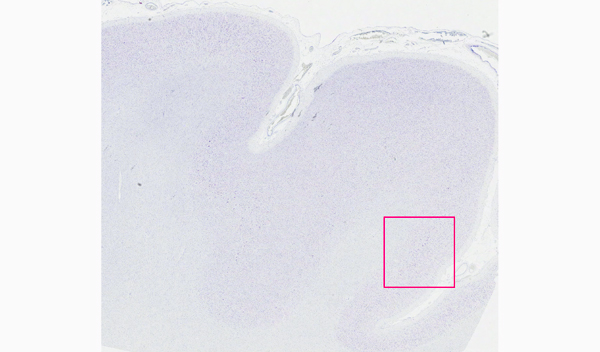

※ クリックすると拡大画像を見ることができます。

背景が白くなるまで分別する。また神経細胞の核は、核小体および核膜が明瞭で染色質の色が薄く染まるのが理想。

SIGMA, Cresyl Violet acetate(pH4.7)使用

写真左)95%エタノール分別、10秒のみ:分別が不十分だと神経細胞全体がべったり青く染まっているため、核、ニッスル小体を識別できない。

写真右)95%エタノール分別、10分間:分別を十分に行うことにより、神経細胞の核、ニッスル小体がはっきりと区別できるようになる。